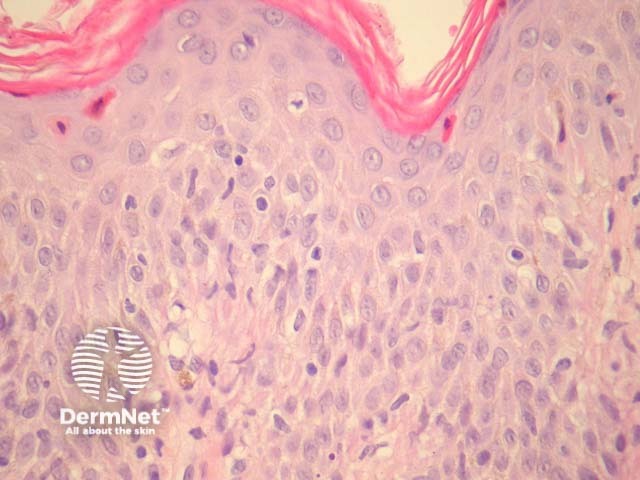

In well established prurigo pigmentosa, histopathologic examination reveals a sparse lichenoid infiltrate which also involves the superficial plexus and parakeratosis (figure 1). There are numerous dermal melanophages in later stages (figure 2). High power examination shows the lichenoid reaction is associated with apoptotic and necrotic keratinocytes present at all levels of the epidermis (figure 3). It is quite common to find a suppurative folliculitis and often hair follicles are filled with bacteria (figure 4).

Figure 3